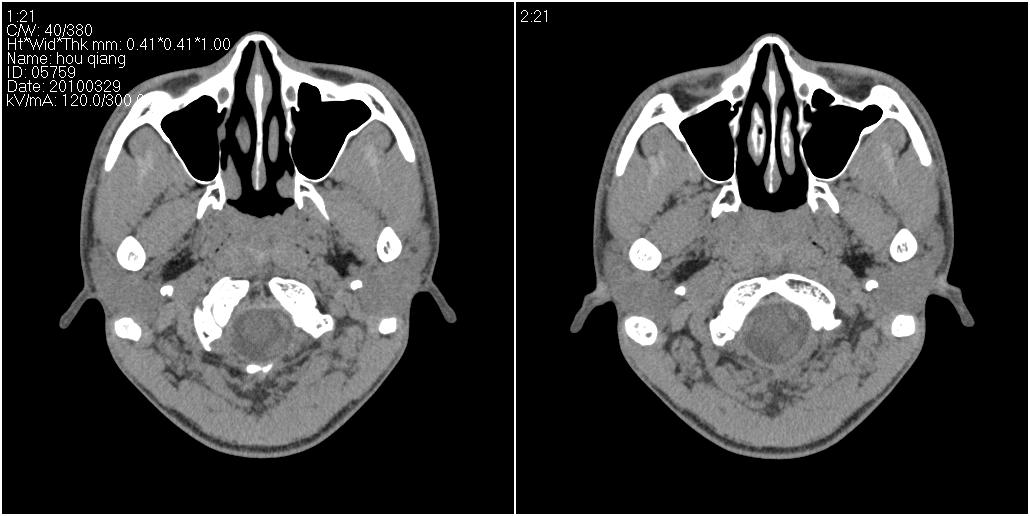

标题: CT25419:男性,18岁。右耳肿、痛5个多月。 [打印本页]

标题: CT25419:男性,18岁。右耳肿、痛5个多月。

右侧中耳乳突炎累及外耳道,鼻咽腺样体肥大。

1)右侧慢性中耳乳突炎并右侧中耳腔及外耳道肉芽肿或胆脂瘤形成。2)鼻咽腺样体肥大。